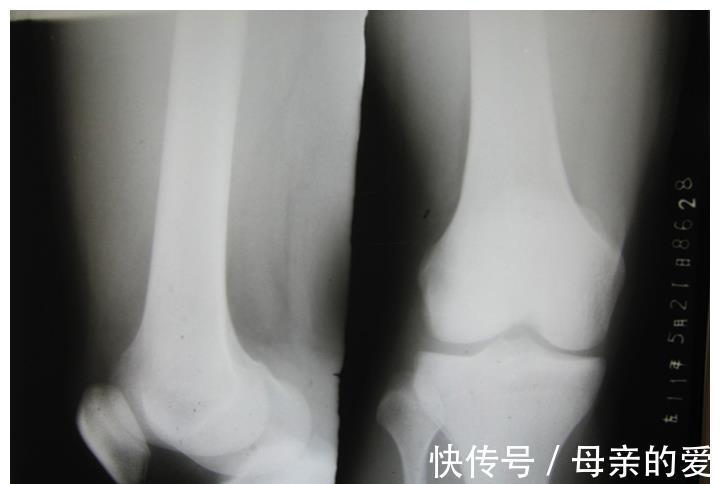

其实最直接的评判孩子长高的一个方法就是骨龄的评估,如果骨龄闭合,无论来不来月经,长高几乎是不可能的了。

如果骨龄还未闭合,身高还是会增长的,

而且骨龄没有闭合的孩子,抓住月经初潮前后的时间适当运动,还是有一个可以增高的机会的。